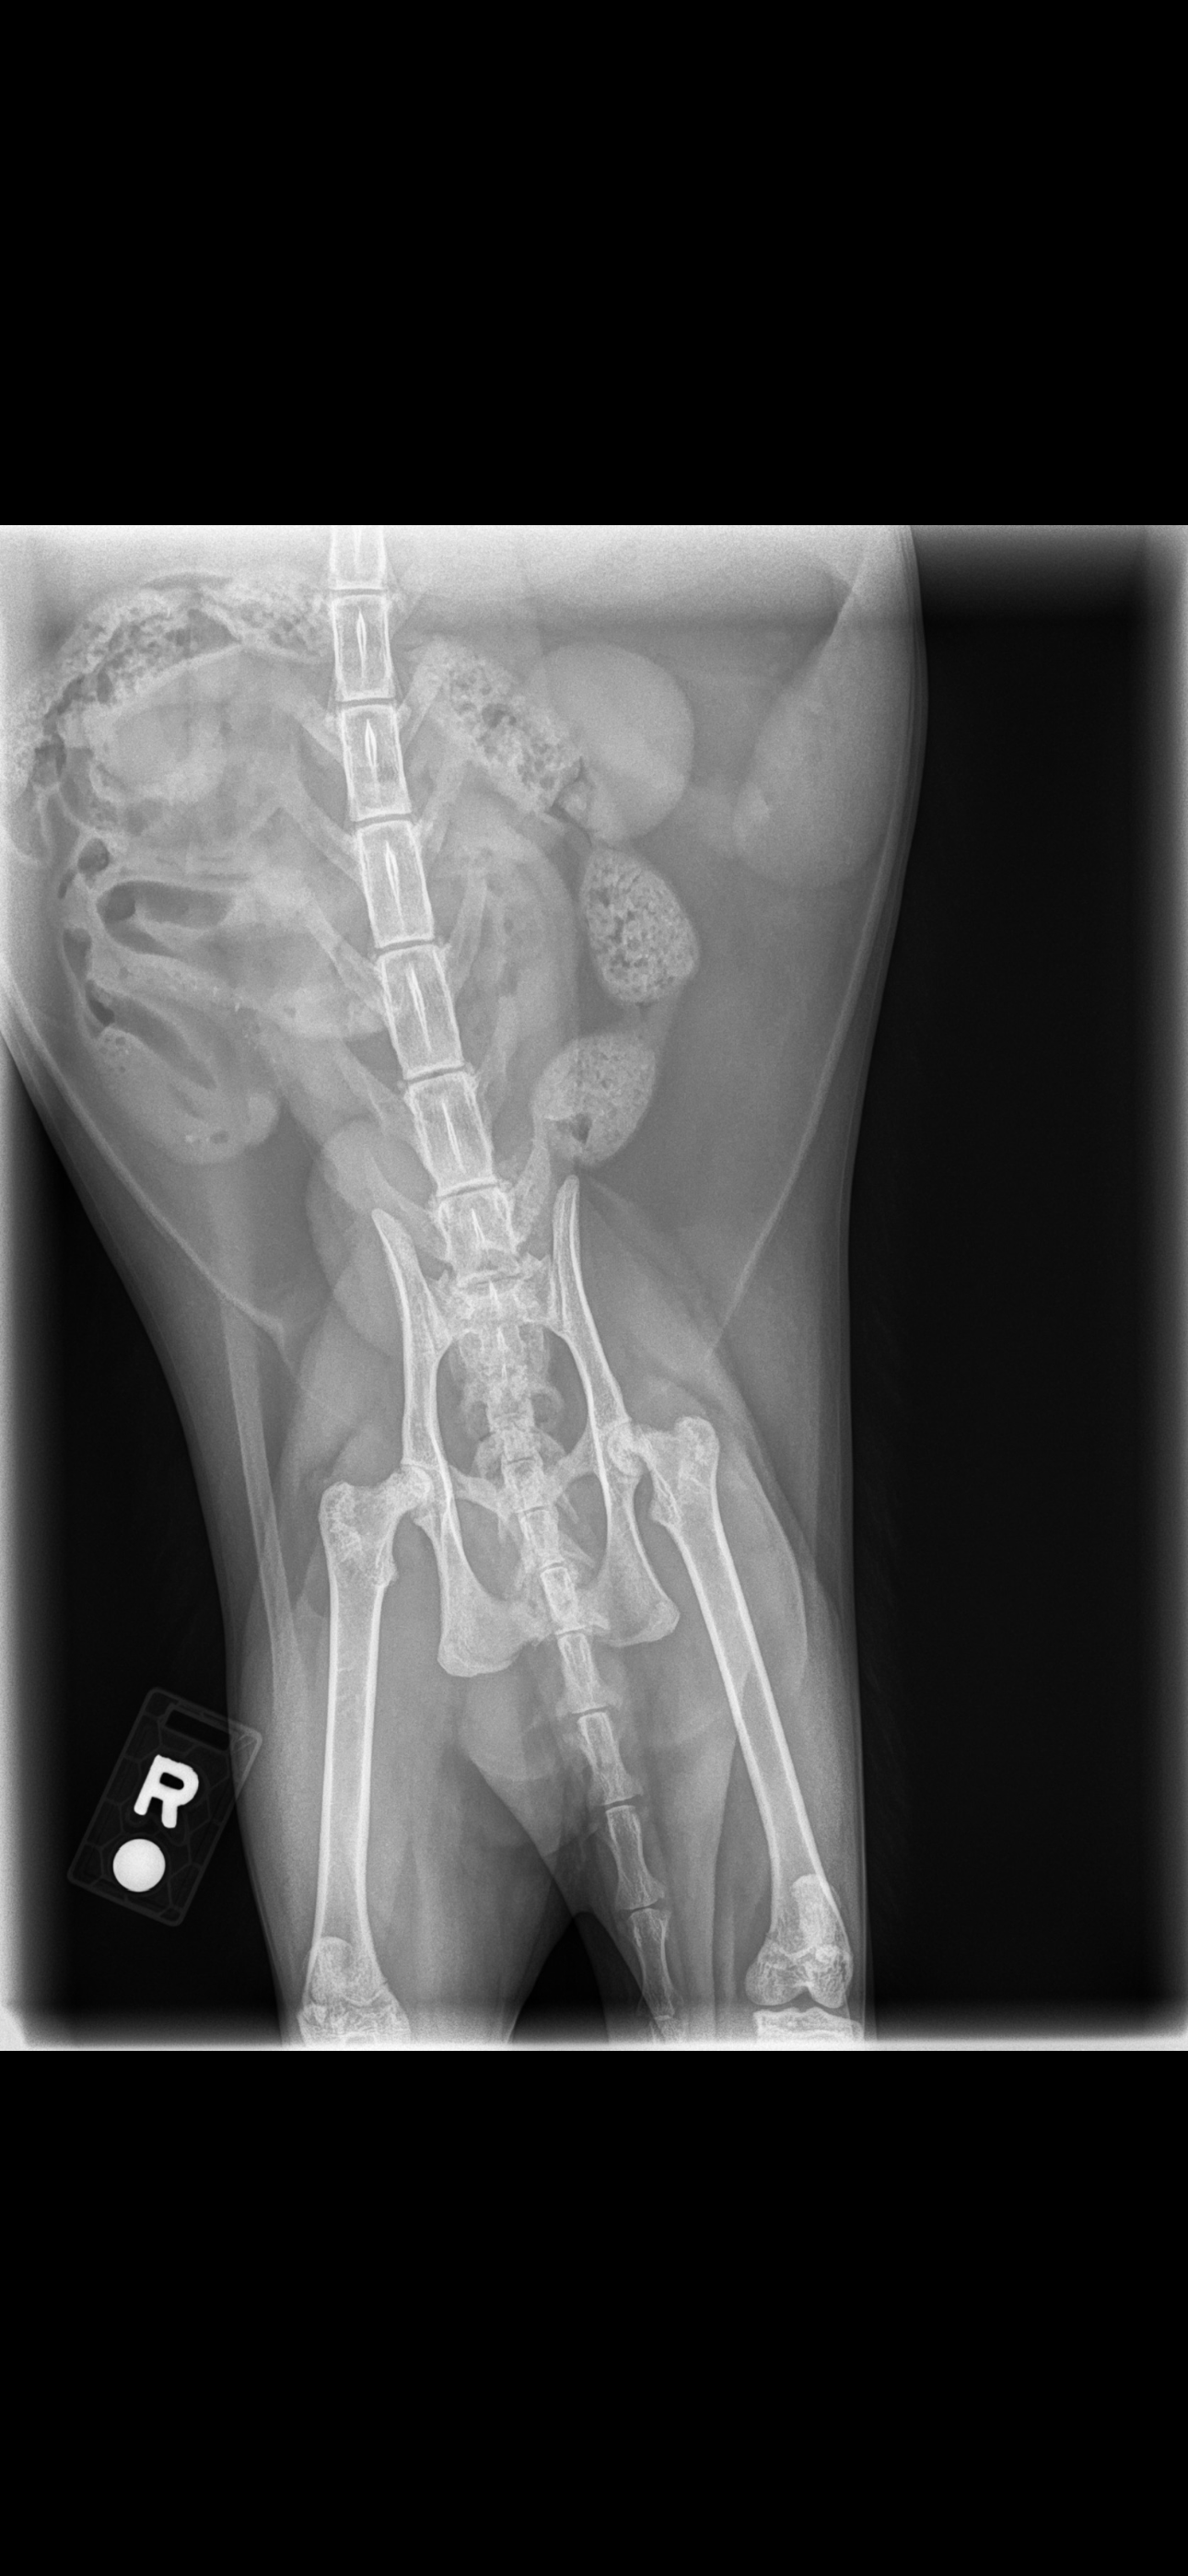

Hello, my name is Kristy and I’m making a GoFundMe for my daughter and her emotional support cat. Unfortunately, we got bad news yesterday after his eight-week checkup from his first hip surgery that he will need a second hip surgery for the right hip. So in order for us to be able to get it, we have to try to earn the money for his second surgery. We need to get the surgery done ASAP before the right hip breaks and he’s unable to walk again. If you could please find it in your hearts to help, we would greatly appreciate it.

Meatball is not even two years old. We’re trying to give him some quality of life. He is also my daughter’s emotional support cat who is very important to her.